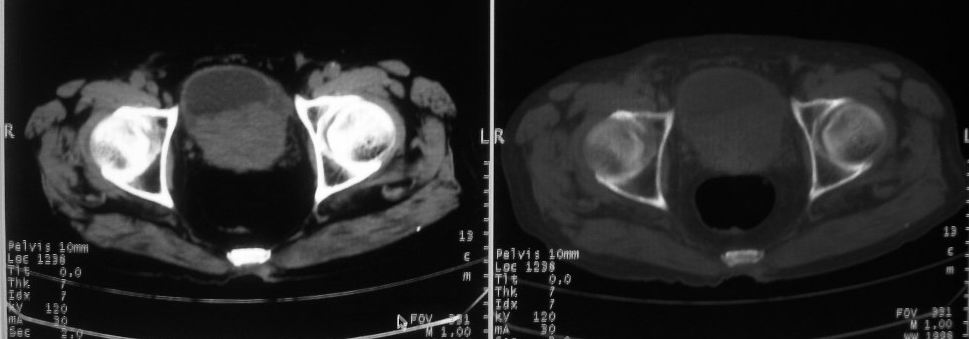

以下是引用zjzjr在2008-10-3 12:59:00的发言:[br]前列腺癌伴左髂骨\\腰椎转移可能性大.

以下是引用卜一在2008-10-3 13:40:00的发言:[br]前列腺癌!左髂骨\\腰椎转移?建议行全身骨扫描!

以下是引用深泽交通医院在2008-10-3 15:33:00的发言:[br]前列腺实性增大伴分叶状,与包膜间隙境界不清;椎体松质区间结节样密度影,考虑:前列腺癌,并椎体成骨性转移